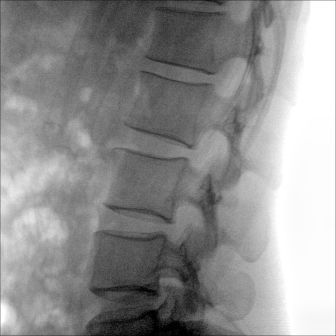

大尺寸動(dòng)態(tài)平板探測(cè)器,高DQE、低噪聲、圖像清晰。采用多分辨率圖像增強(qiáng)處理技術(shù),不同部位不同圖像處理算法,滿足客戶多樣化的需求。

采用智能變頻脈沖透視技術(shù),優(yōu)化圖像質(zhì)量的同時(shí)降低輻射劑量,呵護(hù)醫(yī)患健康